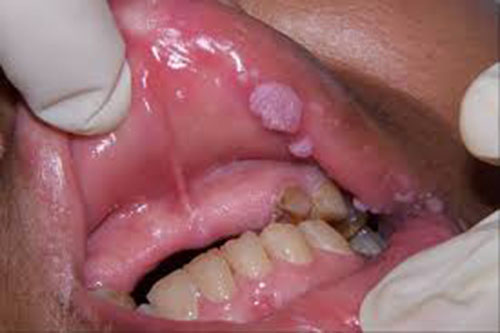

Sùi mào gà ở miệng – họng là những nốt sùi nhỏ li ti có thể mọc riêng rẽ hoặc thành đám ở khoang miệng, chúng có màu hồng, chúng liên kết với nhau nhìn như mào gà hay hoa súp lơ bề mặt xù xì, mềm dẫn đến tình trạng sưng và đau hàm, khó khăn khi giao tiếp, nhai nuốt. Miệng họng có mùi hôi. Nếu để lâu ngày sùi mào gà ở miệng có thể gây ra ung thư vòm họng.

Dưới đây là tổng hợp hình ảnh sùi mào gà ở miệng: